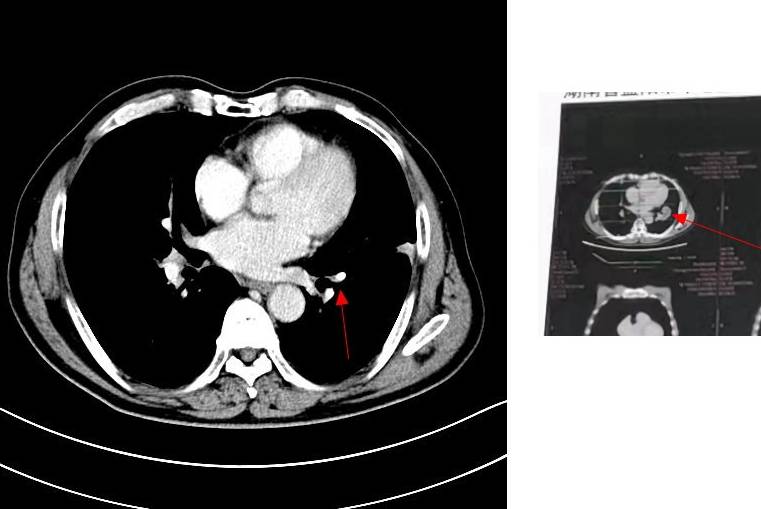

四化放疗后单免半年复查

去拿报告单的时候心如擂鼓,紧张害怕比确诊时更甚!片子上肿瘤区看着应该问题不大。报告单最后才打出来,描述为肿瘤区欠清,不知道为什么但不纠结它。揪着的心还没来得及放下,又看到说左颈部ⅡB区增大淋巴结,均匀强化,医生检查时摸不到,说小于1CM,先观察,也可能是炎症。最近一两个星期老人家说有时候觉得喉咙感觉有东西粘在上面一样,有点不舒服,经常会清一清嗓子,但不怎么咳嗽。会不会是转移?如果是,怎么办?

纵膈肺门小淋巴结倒是一直没动静,估计不是转移了吧。